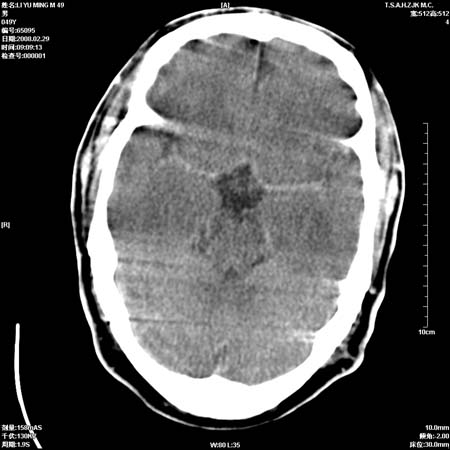

标题: CT12355:男性, 49岁, 主因头痛

男性, 49岁, 头痛, 行ct检查后, 我科一名大夫报了蛛网膜下腔出血, 请大家讨论!

大脑纵裂池及鞍上池应该有蛛血